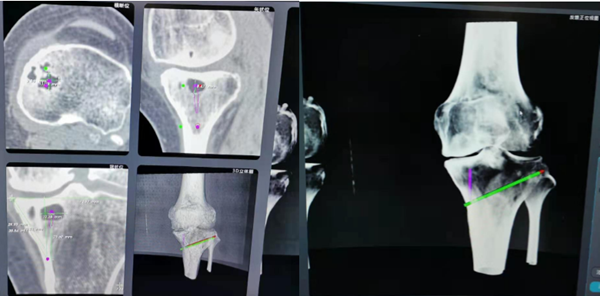

该患者为左侧膝关节内侧骨关节炎,在王坤正教授及王伟主任医师查看病人情况及影像学检查后,建议患者采用机器人辅助下胫骨内侧高位截骨术治疗。同时术前根据患者影像学检查设计并制作了左侧胫骨3D打印模型及3D打印截骨模板。

由王伟主任医师完成了左侧机器人辅助下胫骨内侧高位截骨术。手术通过比对术前CT数据与术中X片完成体表定位,标记克氏针均一次性准确到达设计好的截骨线,截骨撑开后以术前3D打印的个体化楔形模板确定撑开角度,减少了C型臂透视次数,术后患者膝关节疼痛缓解。